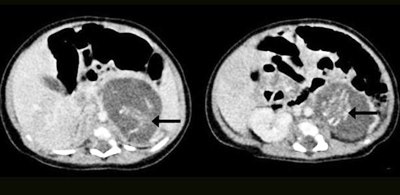

Uma recém-nascida de três semanas passou por cirurgia para retirada de dois pequenos fetos com idades de oito a dez semana que estavam sendo gestados em sua barriga. O caso foi em 2010, mas só foi divulgado ao público na última edição da revista Hong Kong Medical Journal. De início, os médicos acreditaram que o bebê tinha nascido com dois tumores, mas depois perceberam que se tratavam de dois fetos. Os fetos tinham pernas, braços, espinha dorsal, costelas e intestinos. Um pesava 14,2 gramas e outro 9,3 gramas. Ambos tinham cordão umbilical. A cirurgia foi feita por médicos no Queen Elizabeth Hospital, em Hong Kong, e foi bem sucedida. A condição é raríssima. Chamada de foetus in fetu (feto dentro do feto), acontece em um a cada 500 mil nascimentos. Em todo mundo, menos de 200 casos foram registrados. A causa é ignorada. “Era impossível detectar esta condição no ultrassom durante a gravidez, uma vez que os embriões eram muito pequenos”, afirmou o ginecologista Yu Kai-man.”Uma vez que seria impossível que o bebê tivesse engravidado na barriga da mãe, está claro que a fertilização dos dois fetos foi feita no momento da concepção, pelos pais da criança”, concluiu o médico.